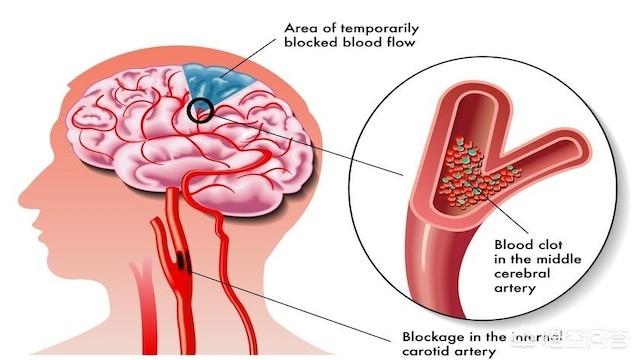

脳梗塞は脳血管障害の一種であり、専門的には「虚血性脳卒中」と呼ばれる。脳血栓症以外にも心房細動などの原因もあります。簡単に言えば、脳梗塞にはいろいろな原因があるが、その中で最も多いのが脳血栓症である。そして、このような脳血栓症の脳梗塞はアテローム性動脈硬化病変、すなわち病理学的基盤がアテローム性プラークに基づくものである。

脳血栓症は、実際には脳梗塞の一種であり、脳梗塞の最も一般的な病態である。脳梗塞の多くは、様々な原因(動脈硬化、動脈炎など)により、脳動脈の主幹または一部の皮質枝の内腔が狭窄、あるいは閉塞し、二次的に局所的な血栓が形成され、その結果、脳組織が虚血や壊死を起こし、それに対応する症状や徴候が出現するものである。

脳血栓症は主に内頸動脈系にみられ、一般に大脳梗塞、分水嶺性脳梗塞、出血性脳梗塞、多発性脳梗塞などの病態がある。

1.脳梗塞と脳血栓症の違い:脳梗塞は、脳梗塞、虚血性脳梗塞とも呼ばれ、脳卒中の一種で、最も一般的な脳血管疾患であり、様々な原因で脳血管が閉塞し、脳組織内の血液と酸素が不足して脳組織が壊死し、一連の重篤な症状が現れます。脳血栓症は脳梗塞の一種で、これも脳血管の閉塞が原因である。アテローム性動脈硬化症血管の肥厚、内腔の狭窄および閉塞、血栓症によって形成される。

本当の名称は「動脈硬化性血栓性脳梗塞」といい、脳梗塞の中で最も多いタイプである。脳梗塞は、脳動脈硬化を基盤とするプラークが破裂・潰瘍化し、血管の血栓・閉塞が促進されることによって起こる脳組織の局所的な虚血・低酸素状態を指す。